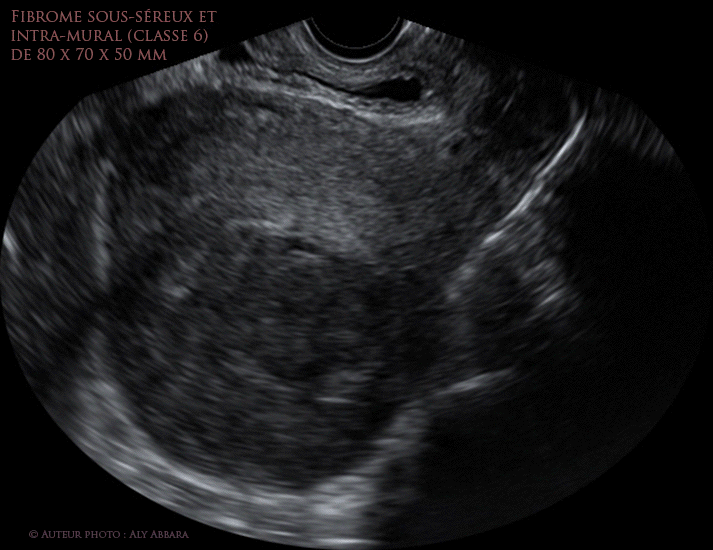

Myome utérin sous-séreux et intramural de classe 6 de FIGO (images échographiques)

Images échographiques animées montrant un fibrome utérin sous-séreux (< 50%) = classe 6 ; de 80 x 70 x 50 mm de diamètre (l'aspect per-opératoire )